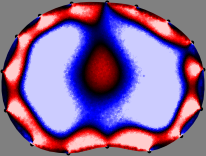

To explain the FER method, we closely examine the correlations among column vectors of the sensitivity matrix , described in Fig. 2. The correlation between and can be expressed as

for [23]. This shows that the column vector is like an EEG (electroencephalography) data induced by dipole sources with directions at locations . Given that two dipole sources at distant locations produce mutually independent data, the correlation between and decreases with the distance between and . Fig. 2 shows a few images of the correlation as a function of for four different positions . The correlation decreases rapidly as the distance increases. In the green regions where the correlation is almost zero, is nearly orthogonal to .

Fig. 2 shows that if and are far from each other, the corresponding columns of the sensitivity matrix are nearly orthogonal. This somewhat orthogonal structure of the sensitivity matrix motivates an algebraic formula that directly computes the local ensemble average of conductivity changes at each point using the inner product between changes in the data and a scaled sensitivity vector at that point: